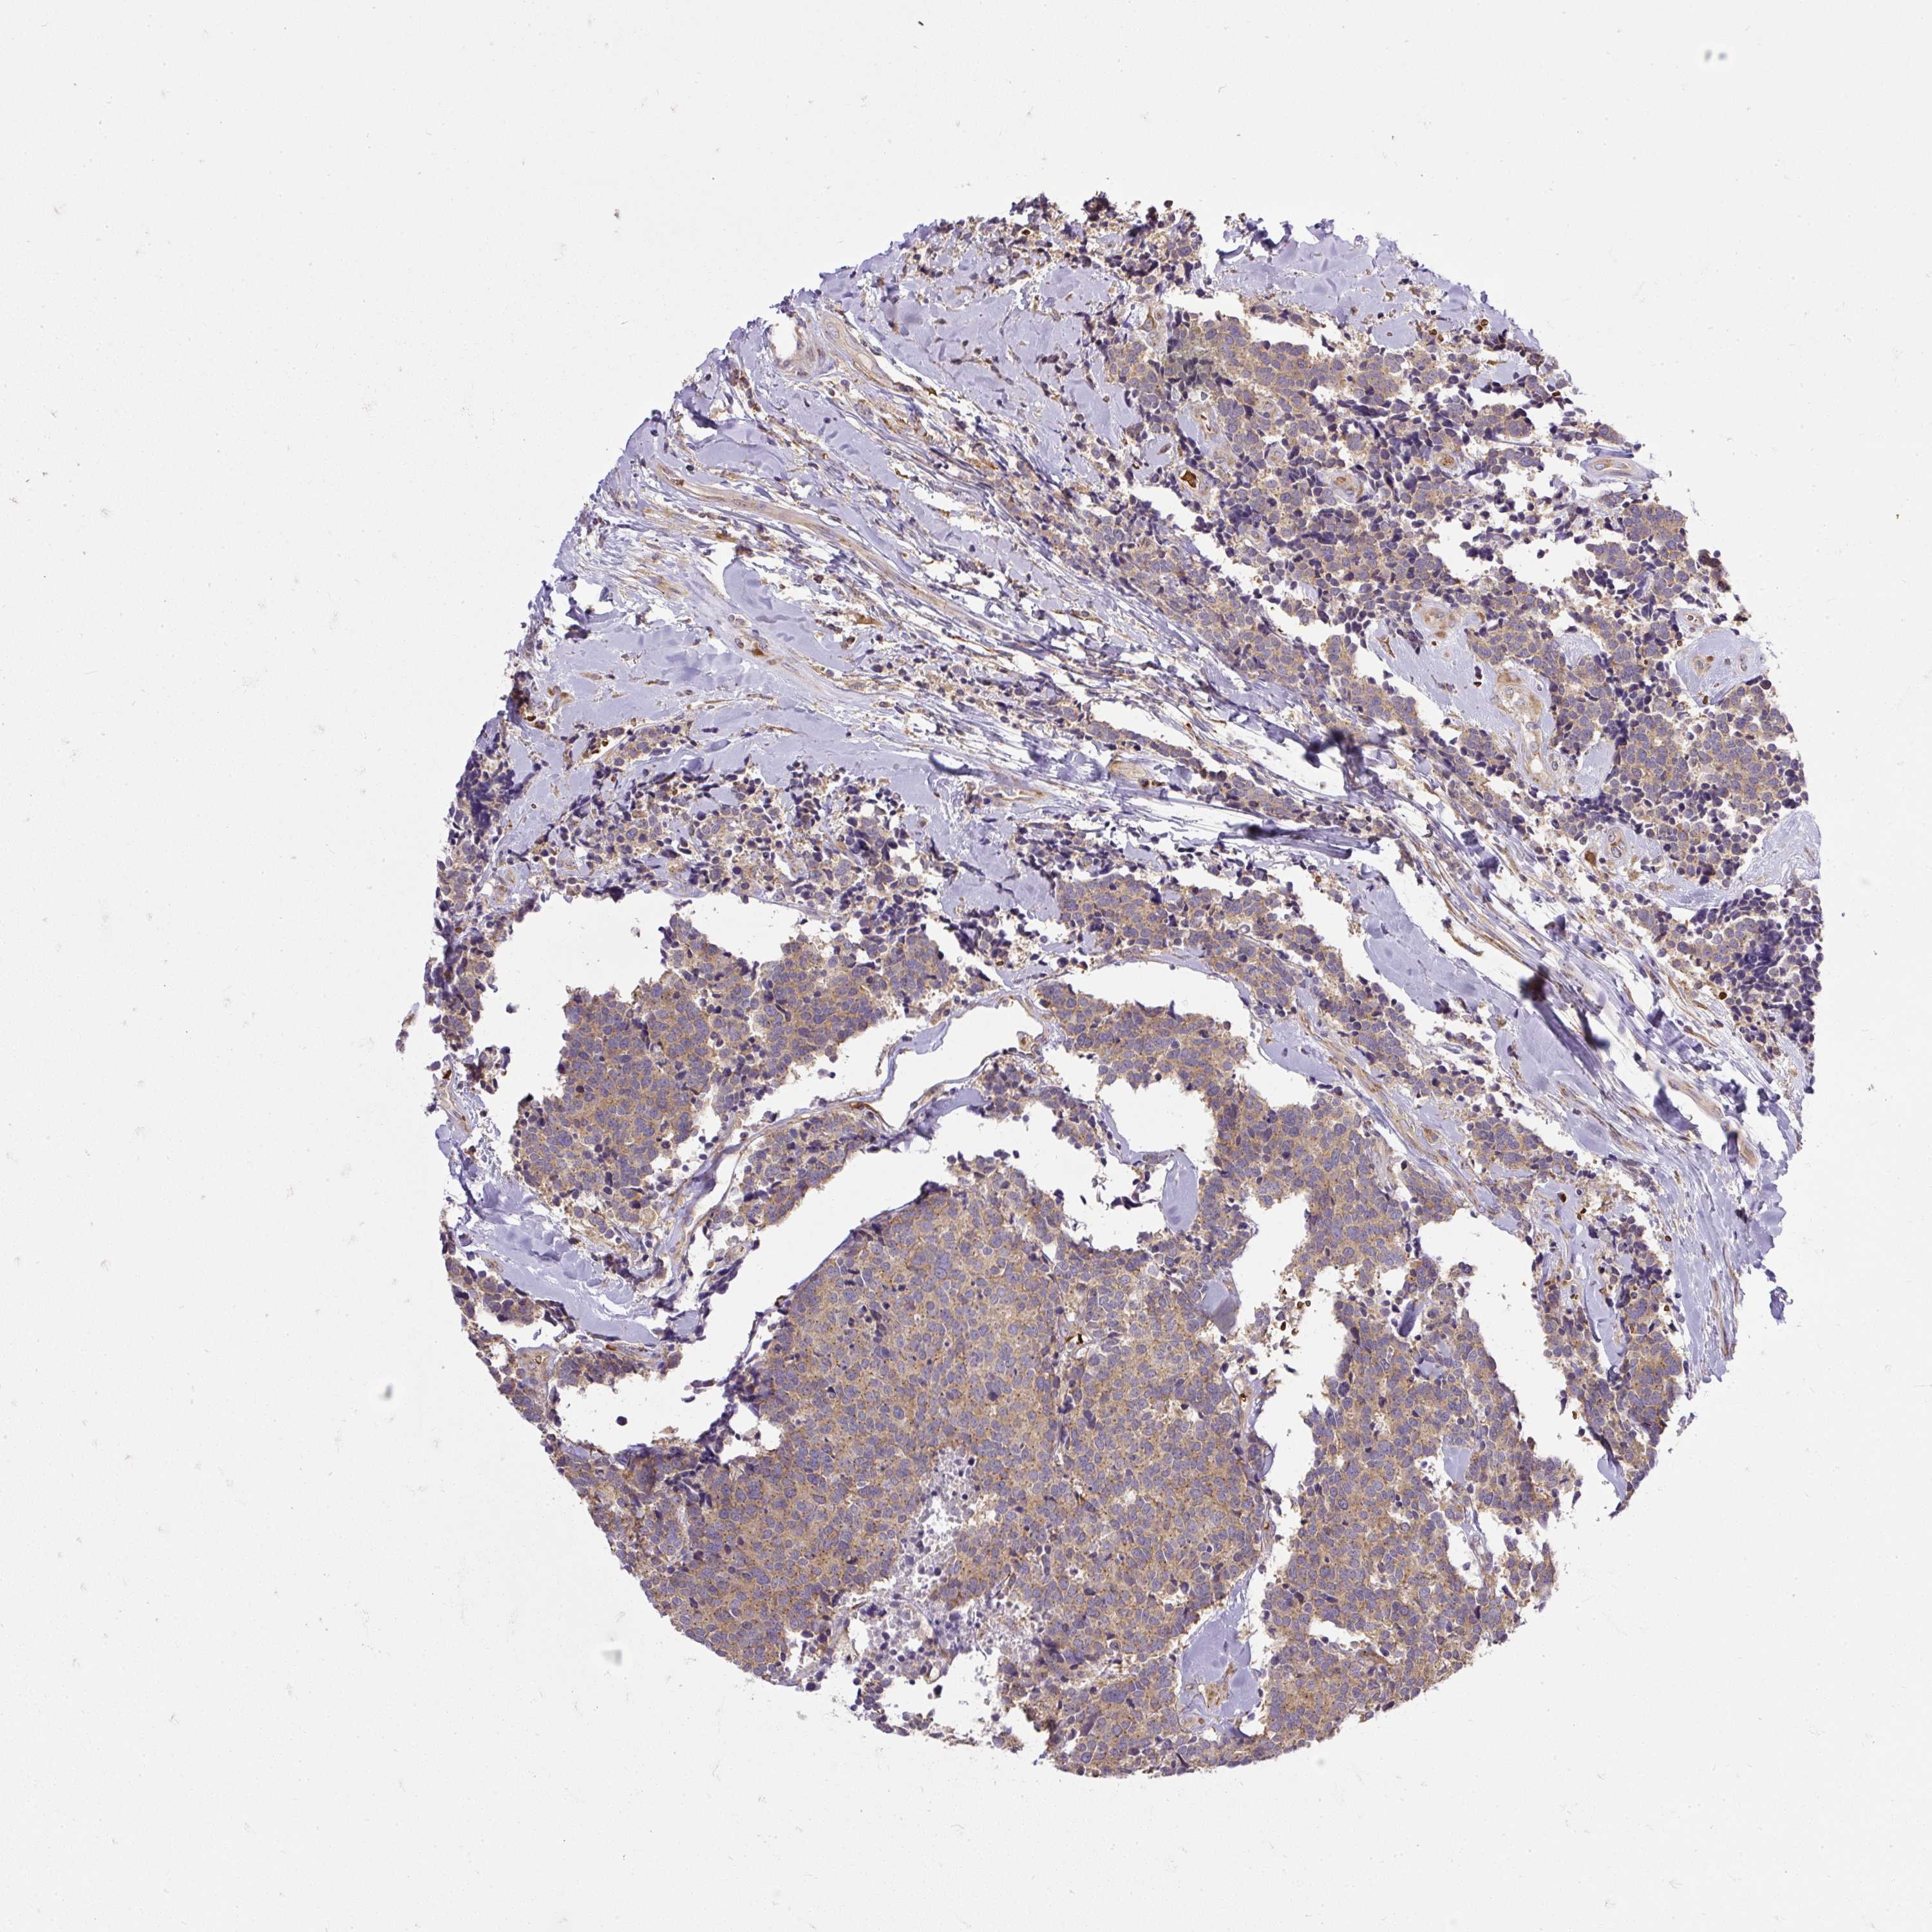

CARCINOID - Protein expressioni

A mouse-over function shows sample information and annotation data. Click on an image to view it in a full screen mode. Samples can be filtered based on level of antibody staining by selecting one or several of the following categories: high, medium, low and not detected. The assay and annotation is described here.

Antibody stainingi

Antibody staining in the annotated cell types in the current human tissue is reported as not detected, low, medium, or high, based on conventional immunohistochemistry profiling in selected tissues. This score is based on the combination of the staining intensity and fraction of stained cells.

Each image is clickable and will lead to virtual microscopy that enables deeper exploration of all samples and also displays staining intensity scores, fraction scores and subcellular localization as well as patient and tissue information for each sample.

Antibody HPA029449

Antibody CAB055509

Staining

High

Medium

Low

Not detected

Intensity

Strong

Moderate

Weak

Negative

Quantity

>75%

75%-25%

<25%

None

Location

Nuclear

Cytoplasmic/membranous

Cytoplasmic/membranous,nuclear

Carcinoid, malignant, NOS

Carcinoma, NOS